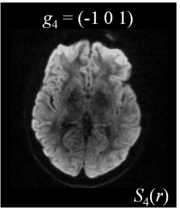

Six axial DW measurements and one non-DW image are shown in Figure 1, along with the corresponding magnetic field gradients . Note the difference in intensity values for different gradient directions.

| (a) | (b) | (c) | (d) |

![]() |

| (e) | (f) | (g) | (h) |